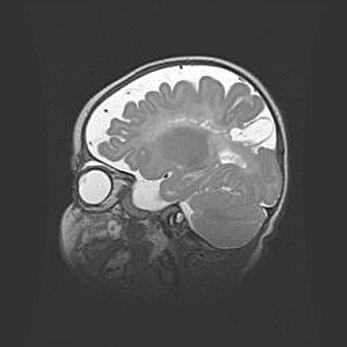

Аномалия Денди-Уокера. Признаки гипоплазии мозолистого тела.

Возраст: 5 месяцев 3 дня

Вес: 5550 г

Пол: мужской

Окружность головы: 39 см

Срок гестации: 40 недель

Аномалия Денди-Уокера – это порок развития головного мозга, для которого характерна триада симптомов: гипотрофия или аплазия червя мозжечка и/или полушарий мозжечка, расширение четвёртого желудочка с формированием ликворной кисты задней черепной ямки, гипертензионная гидроцефалия различной степени.

Гипоплазия мозолистого тела относится к дефектам внутриутробного этапа развития мозговой ткани, возникающим в процессе закладки структур головного мозга, что происходит на начальных этапах развития эмбриона.